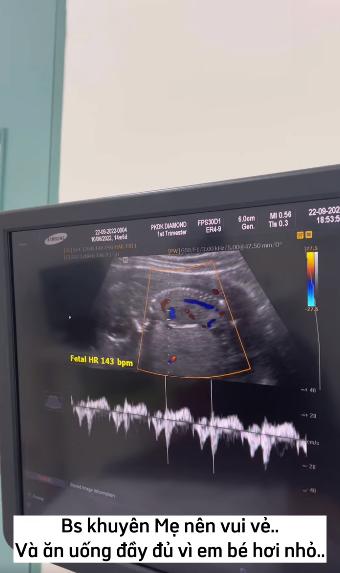

“Mỗi lần đi khám thai, Mật Ong (tên em bé trong bụng - PV) nhảy nhót dữ lắm. Lần này thì nằm im re, lấy tay vò đầu, trông rất buồn mọi người ạ.

Bác sĩ khuyên mẹ nên vui vẻ và ăn uống đầy đủ vì em bé hơi nhỏ. Nghe xong câu đó, em cảm thấy có lỗi vô cùng cả nhà ạ.